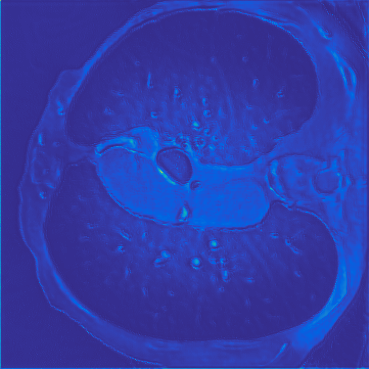

Deep learning-based image reconstruction approaches have demonstrated impressive empirical performance in many imaging modalities. These approaches generally require a large amount of high-quality training data, which is often not available. To circumvent this issue, we develop a novel unsupervised knowledge-transfer paradigm for learned iterative reconstruction within a Bayesian framework. The proposed approach learns an iterative reconstruction network in two phases. The first phase trains a reconstruction network with a set of ordered pairs comprising of ground truth images and measurement data. The second phase fine-tunes the pretrained network to the measurement data without supervision. Furthermore, the framework delivers uncertainty information over the reconstructed image. We present extensive experimental results on low-dose and sparse-view computed tomography, showing that the proposed framework significantly improves reconstruction quality not only visually, but also quantitatively in terms of PSNR and SSIM, and is competitive with several state-of-the-art supervised and unsupervised reconstruction techniques.